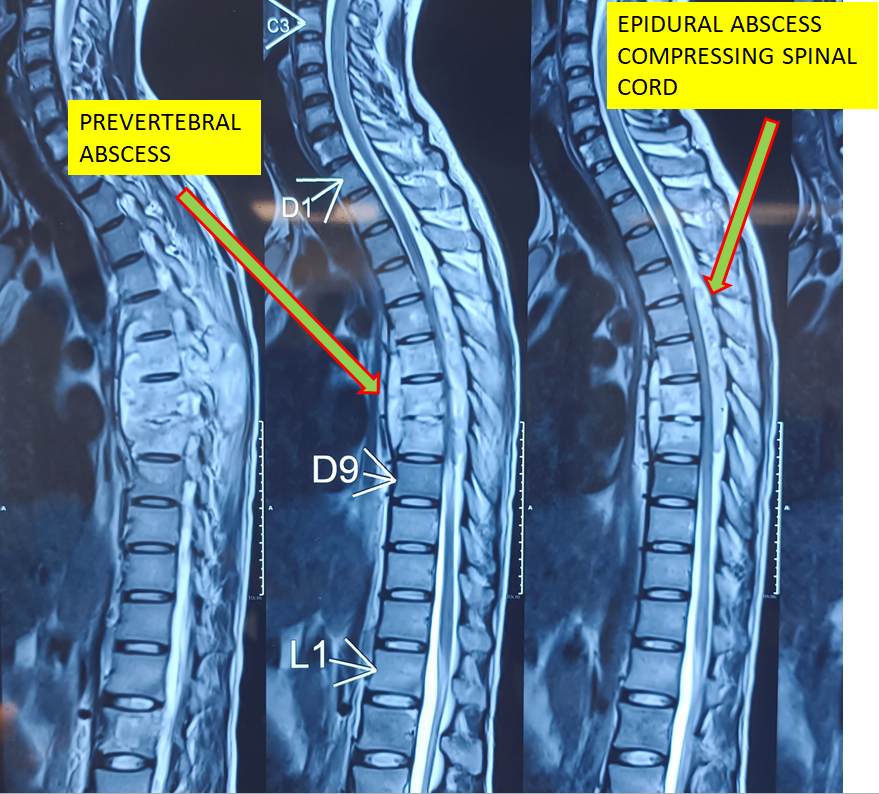

Cervical Myelopathy Expert Care by Dr. Nitish Agrawal – Best Spine Surgeon in Pune Cervical Myelopathy is a serious spinal condition in which the spinal cord in the neck (cervical spine) becomes compressed. This compression is most commonly caused by degenerative changes in the spine, such as cervical disc prolapse,…